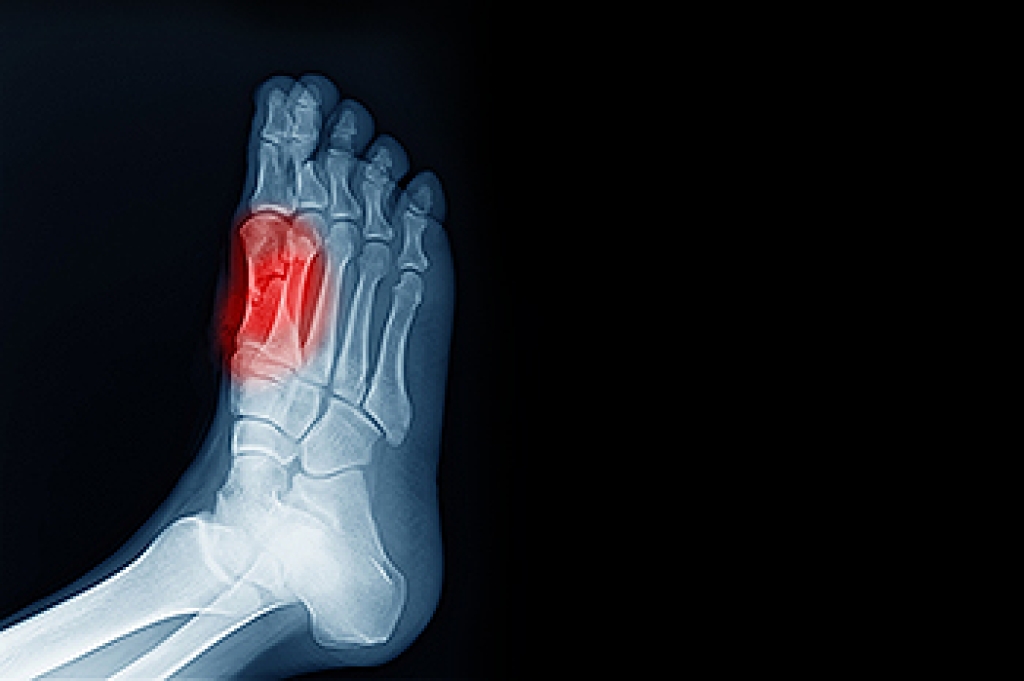

Although many people may have a casual interest in practicing daily foot care, the world of podiatry is expansive and many important pieces of information can help one improve their foot care routine. Importantly, the consumption of alcohol and alcoholic beverages can have a huge impact on one’s everyday foot care. This is because consuming alcohol is linked with several detrimental afflictions on the foot. Namely, drinking alcohol can lead to swelling of the feet, which is also known as edema. The reason for this is that alcohol negatively impacts how a person’s body processes electrolytes. As a result, more water may be present in the body, and swelling of the feet may occur. Additionally, consuming alcohol is linked with gout. Gout is a pesky kind of arthritis that primarily impacts the big toe on the feet. If you or someone you know is struggling with alcohol, consider the impact that the consumption is having on the feet and their health. For more information on alcohol-related foot ailments, please contact a podiatrist.